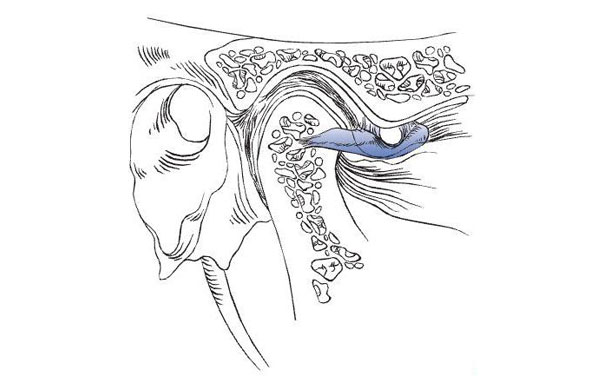

Los terceros molares retenidos (o muelas de juicio) son las últimas muelas en erupcionar en la boca. La dieta moderna y la popularidad de la ortodoncia producen un arco que comunmente no deja espacio para que los terceros molares erupcionen. Un diente se retiene o impacta cuando hay falta de espacio en el arco dental y su crecimiento y erupción son impedidas por la mucosa subyacente, el hueso u otro diente. Estos pueden ser dolorosos u ocasionar infecciones dañando elementos dentarios próximos, como también otros problemas más serios pueden ocurrir si el saco que los rodea se llena de fluidos formando un quiste, o raramente un tumor en sus paredes.

Para realizarse la cirugía no es recomendado esperar a que empiecen a molestar. Una temprana remoción puede resultar en una cicatrización menos complicada, recomendando que la cirugía se realice cuando el paciente es joven adulto para prevenir futuras complicaciones.